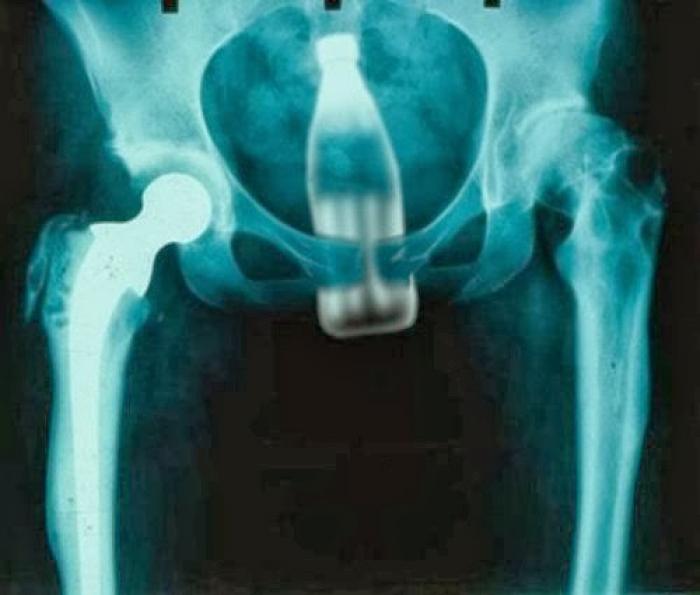

Razele X ne dovedesc că oamenii "pierd" adesea o mulțime de lucruri în propriul corp.